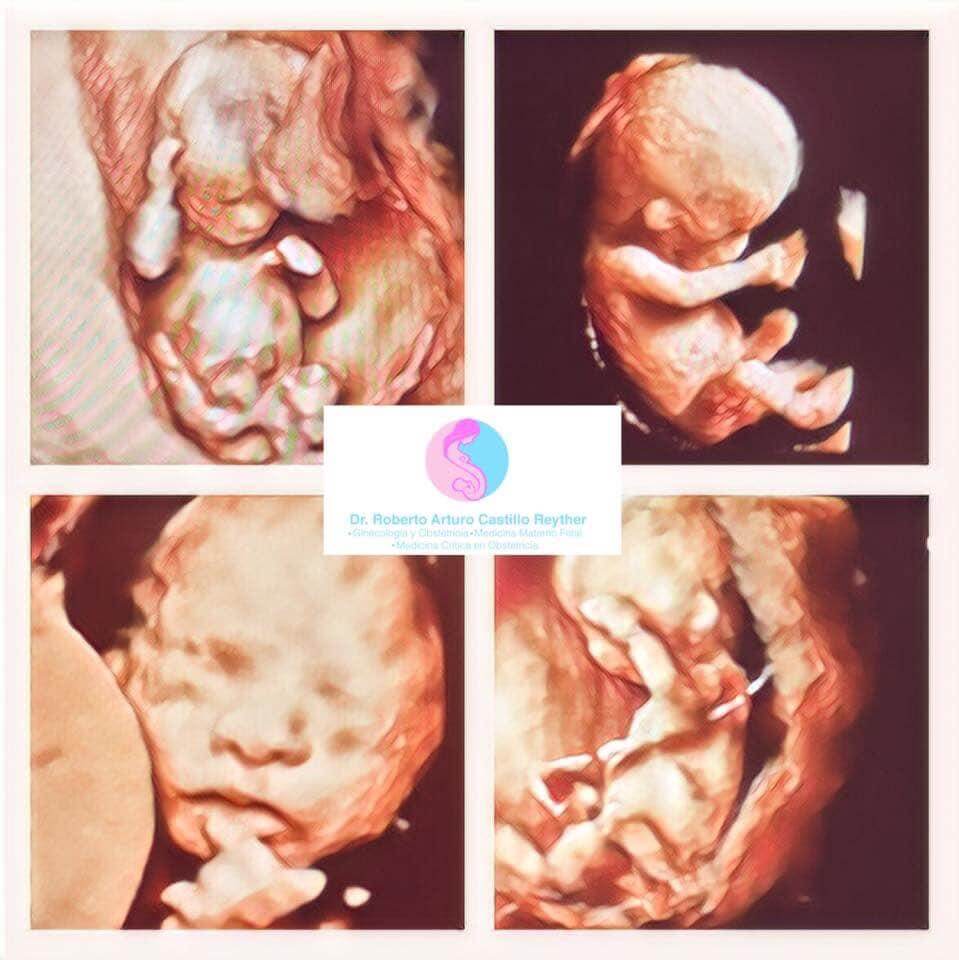

Realiza tamizaje de Síndrome de Down (primer trimestre), alteraciones estructurales (segundo trimestre) y vigilancia del crecimiento (tercer trimestre) a través de Ultrasonido de alta definición, Doppler, 3 y 4 dimensiones. Predicción, prevención y tratamiento especializado de Preeclampsia, parto pre-termino, diabetes gestacional y manejo de enfermedades crónicas durante el embarazo.

con ultrasonido de alta especialidad, Genético 11-14 semanas (detección de síndrome de Down y predicción de riesgo de Preeclampsia), Estructural 18-24 semanas (Anatomía fetal, prevención de parto pretérmino), Crecimiento, 3-4D, embarazo gemelar y doppler.